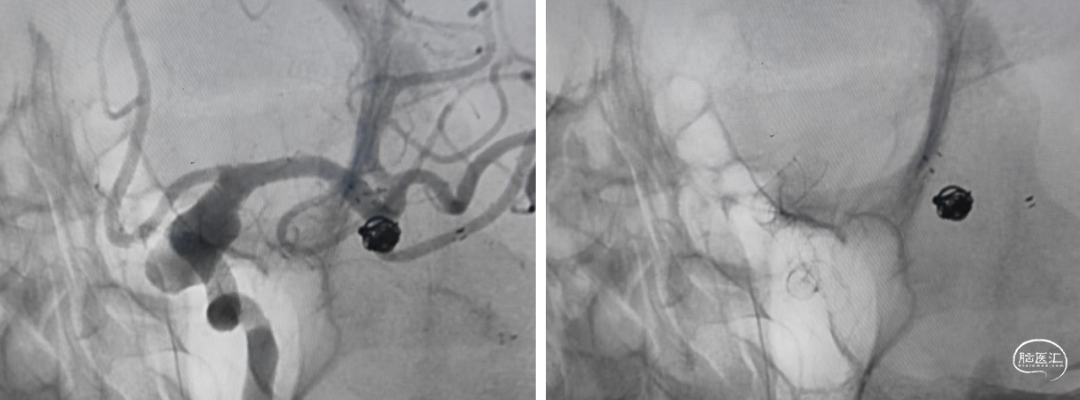

手术方案

左侧颈内动脉末端夹层动脉瘤:Nuva®血流导向密网支架植入。

术前测量左侧颈内动脉末端夹层动脉瘤长10mm,瘤体最宽处8mm,载瘤动脉近端血管直径约4.2mm,远端血管直径约3.5mm。拟选用Nuva®血流导向密网支架 TJED-D-4.5-30(预期血管直径长度:4.0mm*40mm)。

随即进行颈内动脉末端夹层动脉瘤的治疗,工作位置角度下,交换XT-27支架微导管,通过辅助支架至大脑中远端。

沿支架微导管输送Nuva®血流导向密网支架,待支架头端显影点与微导管齐平,支架输送到位,整体回撤微导管和支架至合适的锚定位置,在大脑中M1中段原位释放密网支架。

支架顺利打开,造形可见支架贴壁良好。